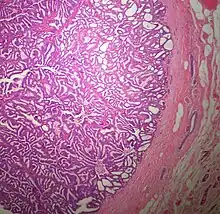

The microscopic histopathology of typical PDCIS lesions (refer to adjacent high-power photomicrograph) prepared with a hematoxylin and eosin stain consists of mammary ducts that have papillary fronds (i.e. thin, finger-like or leaf-like structures) lined with one or several layers of neoplastic, columnar-shaped epithelial cells (i.e. tall, narrow cells with their nuclei close to the site of their ductal attachment).[4] The fronds have branching fibrovascular cores. Epithelial cells lining the fronds' inner surfaces commonly form solid, cribriform (i.e. large nests of cells perforated by many rounded, variably sized spaces), or micro-papillary patterns. There may be a second population of epithelial cells lining the papillae that have abundant clear cytoplasm in addition to the usual neoplastic epithelial cells which line the papillae. These cells, which are not myoepithelial cells, have been termed globoid cells.[7] They have eosinophilic cytoplasm (i.e. pink or red cytoplasm due to its uptake of eosin stain).[6] PDCIS tumors with these cells have been termed dimorphic variants of PDCIS.[3] Myoepithelial cells are typically present at the periphery of the fronds but absent within the involved ducts.[4][7] The presence of a fibrous capsule and/or absence of peripherally located myoepithelial cells are strong indicators that the tumor is an ESP rather than a PDCIS.[3] PDCIS tissues may also contain areas of "Comedo-type necrosis", i.e. areas where dead cells have accumulated.[6]

Microscopic histopathological analyses of SPC lesions (refer to adjacent high-power photomicrograph) generally show tumors with multiple circumscribed nodules of expanded ducts filled with neoplastic epithelial cells which may appear spindle-shaped or plasma cell-like, have red to pink cytoplasm due to the uptake of eosin after staining with hematoxilin & eosin, and eccentrically-placed nuclei. Rarely, signet ring-shaped cells are present. The tumors may have cystic and hemorrhagic areas. Myoepithelial cells are found within and at the periphery of these tumors. The papillary architecture seen in the other SCB types is in general not apparent; rather, pseudo-rosettes (i.e. radial arrangements of neoplastic cells around small blood vessel) and nuclear palisading (i.e. parallel arrangements of the nuclei in rows of tumors that resembles picket fences) around stromal cores (i.e. supporting tissues) may be seen. SPC tumor tissues typically (>50% of cases) have areas of neuroendocrine differentiation. The presence of these areas strongly supports the diagnosis of SPC.[21] The signet ring-shaped cells in these tumors contain cytoplasmic mucin-containing vacuoles which push their cells' nuclei to one side.[10] Mucin may also occur outside of cells in these lesions. The presence of signet ring-shaped cells bearing mucin-containing vacuoles with or without extracellular mucin strongly supports the diagnosis of SPC. SPC is considered invasive when the tumor nests have a characteristic jigsaw growth pattern with ragged and irregular margins with the loss of myoepithelial cells at the site(s) of invasion.[21] Rarely, invasive SPC occurs with nearby invasive carcinoma of NST, lobular carcinoma, cribriform carcinoma, or tubular carcinoma breast tumors.[3]

Since many of the earlier published cases of IPC actually appear to be variants of invasive EPC or SPC, there is little consistent pathological data on IPC.[7] Studies on the microscopic histopathology of IPC have reported finding (refer to the adjacent high-power photomicrograph): 1) blunt papillae or ductal structures consisting of neoplastic epithelial cells surrounding a fibrovascular core;[1] 2) papillae located in dilated ducts and variably sized microcysts plus foci of necrosis (i.e. dead cells);[4] 3) tumors totally dominated by fibrovascular cores covered with neoplastic epithelium cells;[3] and 4) tumors showing >90% papillary morphology invading nearby breast tissue and/or sub-mammary chest muscles.[22] Studies do agree that IPC tumors have, by definition, one or more sites that have invaded nearby breast and/or muscle tissue, lack myoepithelial cells at their invasion sites, and generally lack a peripheral fibrous capsule; these features are important for diagnosing IPC.[6][7][20][22] Rarely, ductal carcinoma in situ lesions are present near IPC.[3] A retrospective histopathological analysis of the tumor tissues in 1,147 individuals with IPC reported that 89.3%, 83.4%, and 2.4% of the cases had tumor cells which respectively expressed the estrogen receptor, progesterone receptor, and HER2/neu protein (however, 46.4% of the cases were not tested for the HER2/neu).[1] In a second histopathological study of 44 individuals diagnosed with IPC, 72.7% had tumor cells that expressed the estrogen receptor, 72.7% had tumor cells that expressed the progesterone receptor, and 13.6% had tumor cells that expressed the HER2/Neu protein.[22] No specific genetic alterations have been as yet been clearly associated with the tumor cells in individuals diagnosed with IPC.[6]